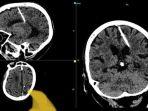

Wanita Rusia Usia 80 Tahun Hidup dengan Jarum di Otaknya, Korban Krisis Perang Dunia II

Wanita Rusia berusia 80 tahun ini hidup dengan jarum menancap di dalam otaknya. Ia adalah korban krisis Perang Dunia II di Uni Soviet.